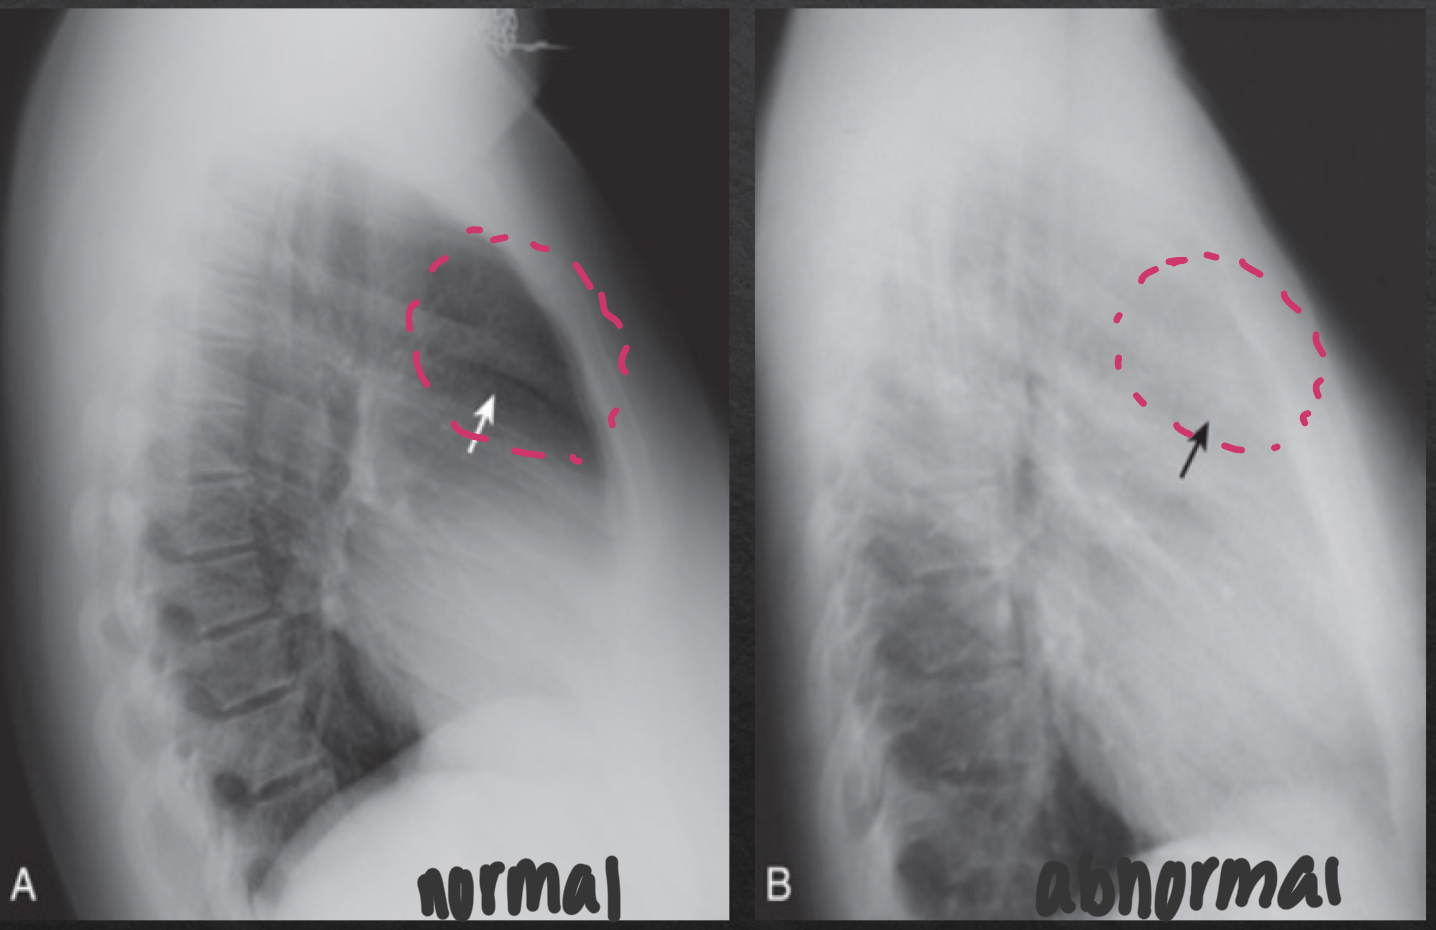

retrosternal space

NORMAL

lucent crescent btwn sternum and ascending aorta/anterior heart

ABNORMAL

soft tissue density filling normal space behind the sternum